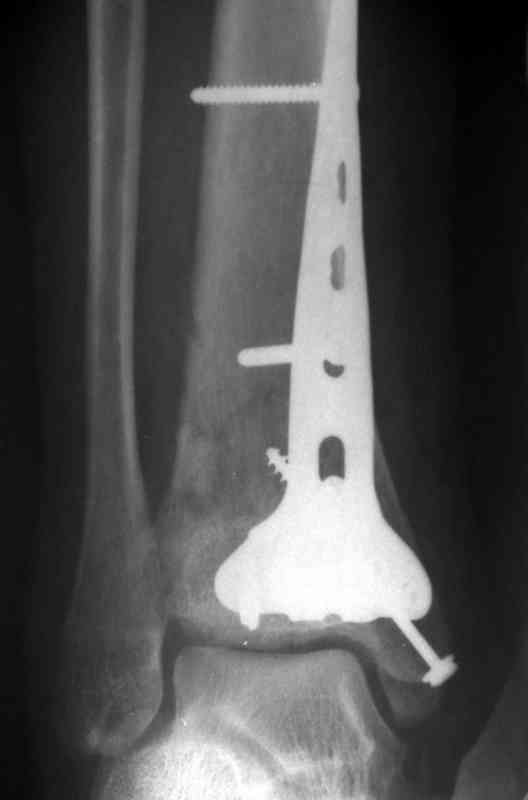

Посылаю результат лечения предыдущего больного через год.

С уважением Дрягин

Кстати, при переломах переднего края по классификации АО В-3 при переломах пилона пластина укладывается по передней поверхности. Она достаточно тонкая и эластичная, не надо этого бояться. Посылаю три снимка.